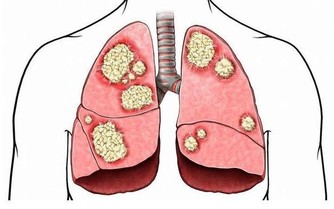

但患了胃潰瘍、十二指腸潰瘍、胃癌或腸癌等疾病也會引起消化道出血引起黑便,患者會伴隨腹痛、腹瀉、噁心、嘔吐等不適症狀。

如果腸道裡面出現了腫瘤細胞,這些腫瘤細胞就會快速的繁殖,導致腸道的空間變窄,大便也因此會變細,尤其是直腸部位出現腫瘤細胞之後這種情況更加明顯。

所以,一旦發現自己的大便變得越來越細就要及時到醫院檢查治療,以免腸道完全阻塞之後無法順利排便。癌症進入晚期之後會大大的增加治療的難度,使生命受到嚴重的威脅。